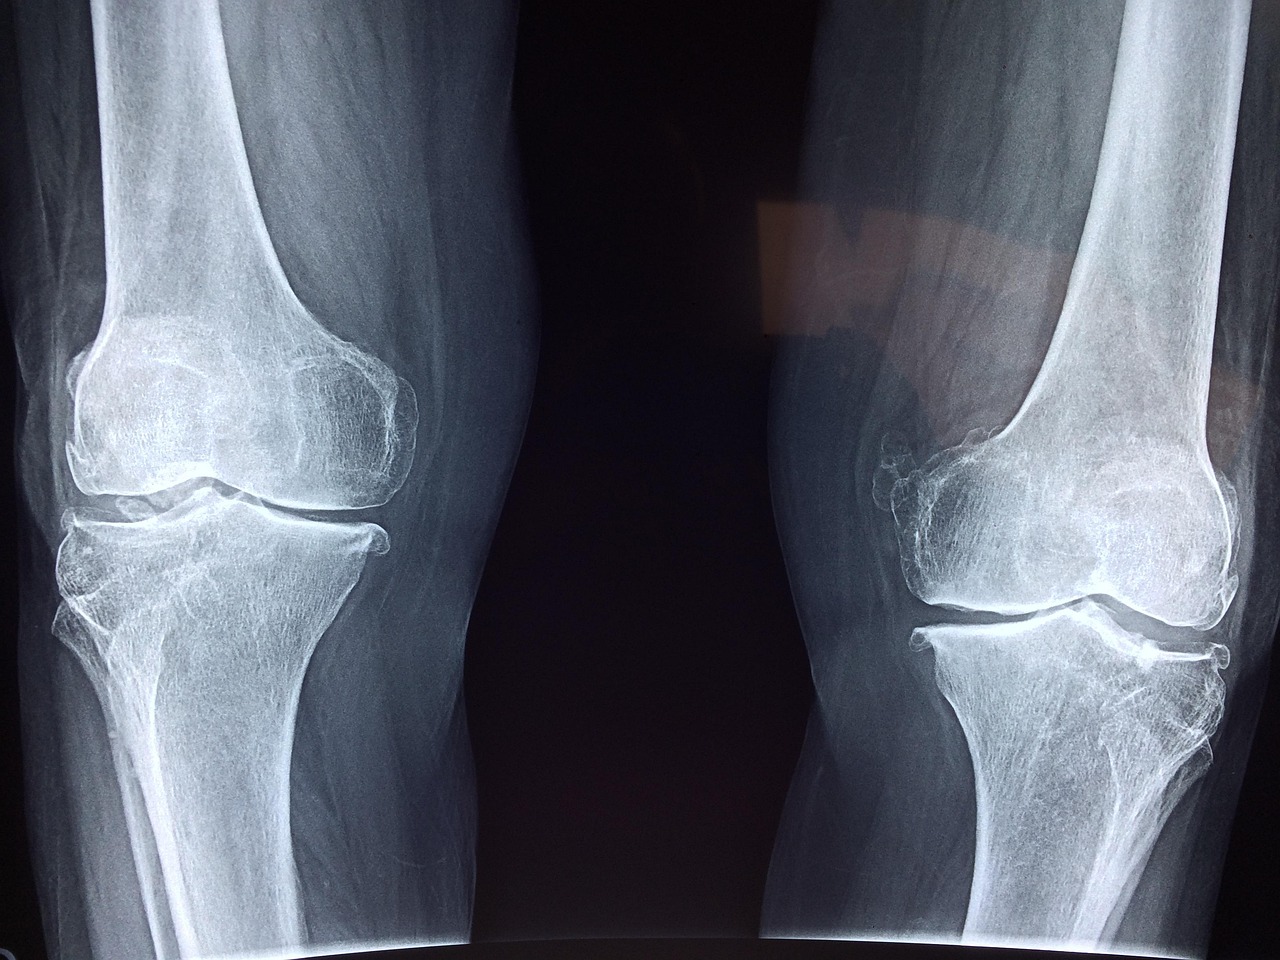

Cartilage is primarily composed of specialized cells known as chondrocytes embedded in a dense extracellular matrix. This unique structure gives cartilage its strength and resilience, allowing it to withstand compressive forces. Cartilage serves several essential functions in the human body, including shock absorption and providing a smooth contact surface for joints. It also plays a role in the growth and development of long bones during childhood and adolescence. In athletes, maintaining the integrity of cartilage is crucial, as joint injuries can lead to early-onset osteoarthritis if not properly managed. Additionally, the type of cartilage varies throughout the body; for example, articular cartilage covers the ends of bones in joints, while fibrocartilage is found in the intervertebral discs and menisci of the knee. The health of cartilage is critical in sports and physical activity, as it directly impacts performance and mobility. Ongoing research into the biochemical pathways involved in cartilage degradation is paving the way for innovative treatments that enhance cartilage repair and overall joint health. Understanding the complexities and functions of cartilage could lead to breakthroughs in managing sports-related injuries effectively.